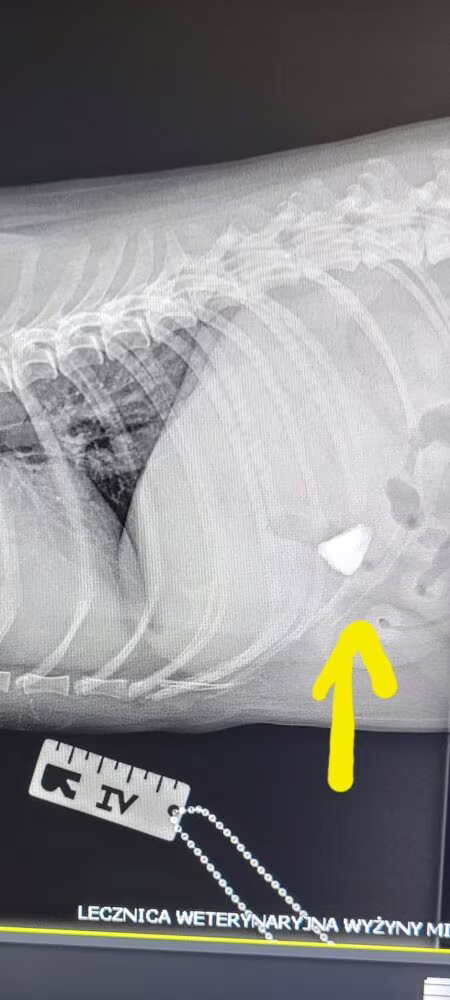

Na zdjęciu RTG widoczny był kamień, który został usunięty chirurgicznie.

Pikuś trafił do nas na RTG klatki piersiowej. Przy okazji odkryliśmy… pewien niespodziewany przedmiot 🙀🔍